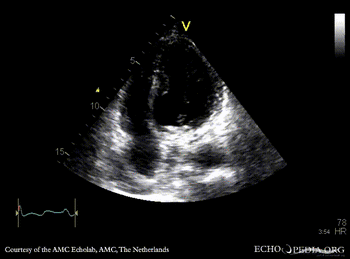

| A4CH: aneurysm of basal inferior wall | |